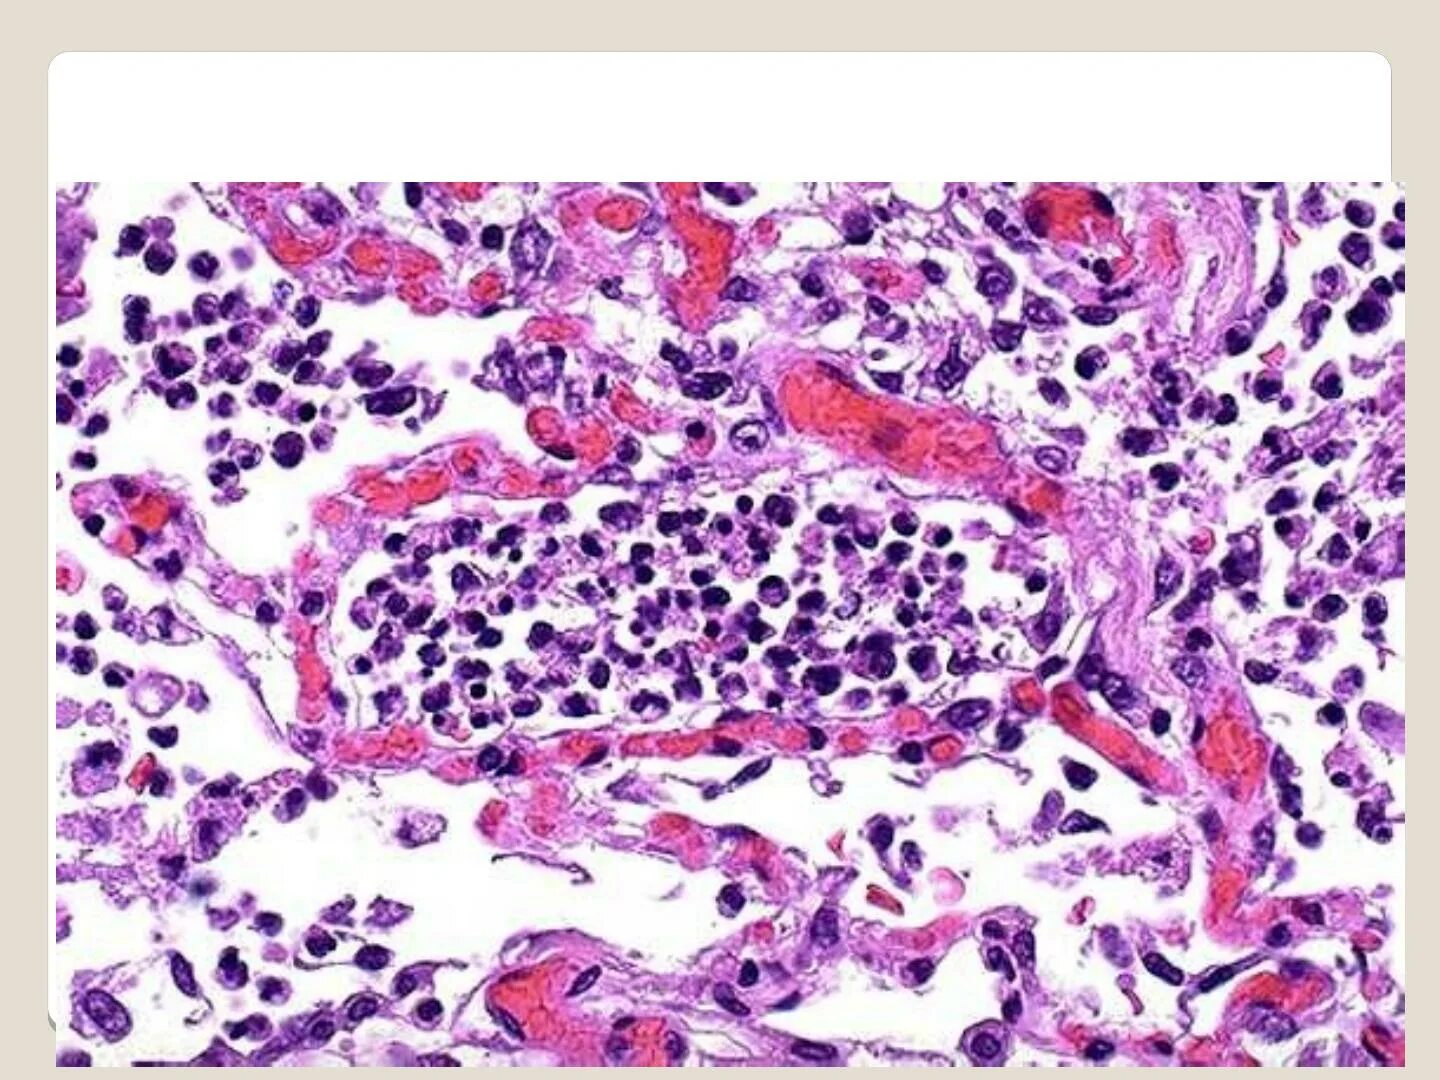

Серозный выпот